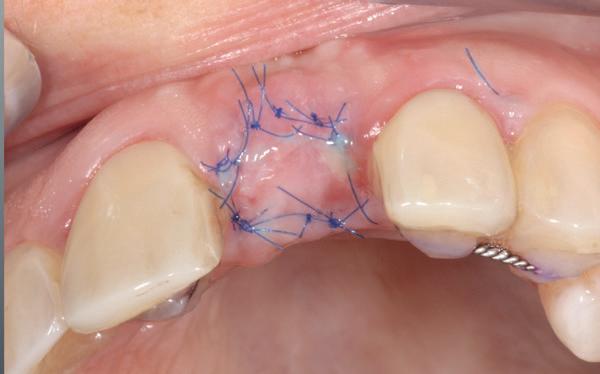

Er werd meer bekend over de gedragingen van het bot rond de “microgap” en daarmee kwam er meer begrip over hoe een implantaat goed te plaatsen in de esthetische zone. In het midden van de jaren negentig kwam daar de kennis bij hoe, op een verantwoorde manier en met behulp van guided-bone-regeneration, een implantaat in de esthetische zone te plaatsen (afbeelding 6-10).

Van vooral functionaliteit verschoof de indicatie naar esthetiek. De zachteweefselchirurgie en vaak voorbehandeling van zachte weefsels voor implantologie kreeg veel meer aandacht (afbeelding 11-14).